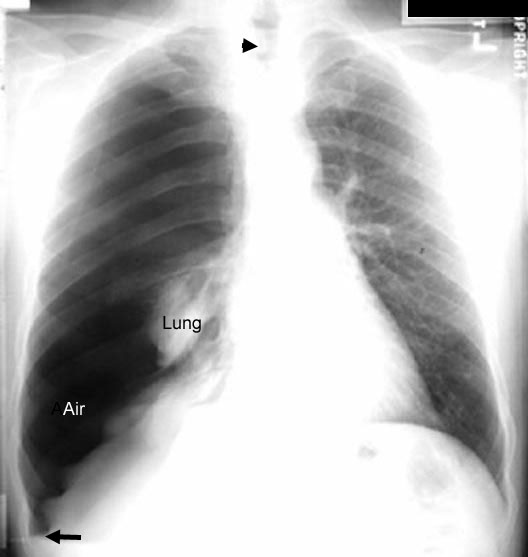

Relaxation Atelectasis / Pneumothorax

The CXR on the left reveals a right pneumothorax.

In this instance, the loss of negative pressure in the pleura permits the lung to relax and become atelectatic due to elastic recoil.  The right lung is now devoid of air and is atelectatic. Note the atelectatic lung adjacent to the right heart silhouette.

Black arrow is pointing to deep sulcus sign. The loss of negative pressure in pleural space releases the chest wall to TLC position. Diaphragm is part of the chest wall and moves downwards creating the deep sulcus sign.

Black arrowhead is pointing to trachea.

There is a common misconception that atelectasis is due to compression. I disagree with that concept as is given in textbooks. Lung relaxes to the atelectatic position due to elastic recoil and not due to external compression.